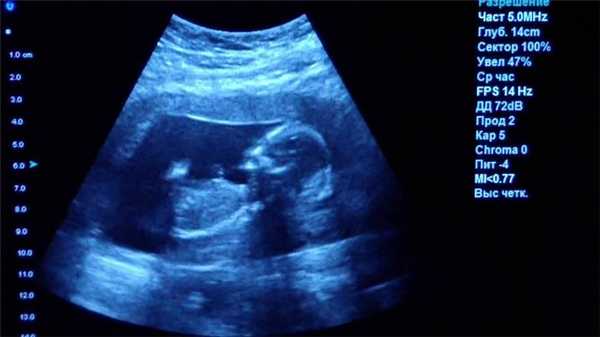

Ультразвуковое исследование (УЗИ)

Главное преимущество такого способа исследования — безопасность. УЗИ можно делать даже беременным женщинам, кроме того, приборы УЗИ-приборы мобильны, их легко можно поставить в палате пациента, чтобы наблюдать за состоянием органов и кровотока в режиме реального времени.

Однако УЗИ не может обеспечить картинку высокой чёткости, поэтому использование этого метода исследование ограничено, например, при помощи УЗИ нельзя диагностировать заболевания ЖКТ.